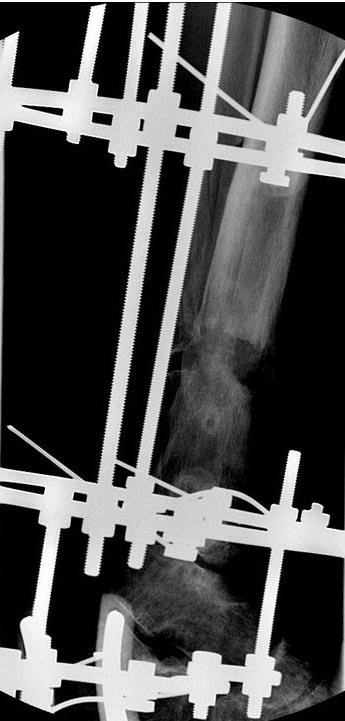

В феврале 2014 г выполнил первым этапом: Фиксацию ложного

сустава в АНФ с восстановлением осей сегментов. Через семь дней БИОС с

рассверливанием.

После операции - вальгус голеностопного сустава. Гладкое течение

послеоперационного периода. Нагрузка по переносимости боли. Через 6

недель динамизация, через 2 недели стали мигрировать 2 фронтальных

винта. Пытался подкрутить, пришлось удалить.

Через 6 мес. контроль - линия ложного сустава прослеживается, но имеется

периостальная костная мозоль.

Не хватает стабильности.